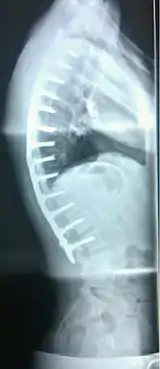

| extreme case of Scheuermann's disease | |

Scheuermann's disease, showing various measurement of kyphotic/lordotic degrees and their supplementary angles. Notice the signature 'wedging' shape of the four vertebrae in the lower thoracic area. The other vertebral bodies are otherwise normal.